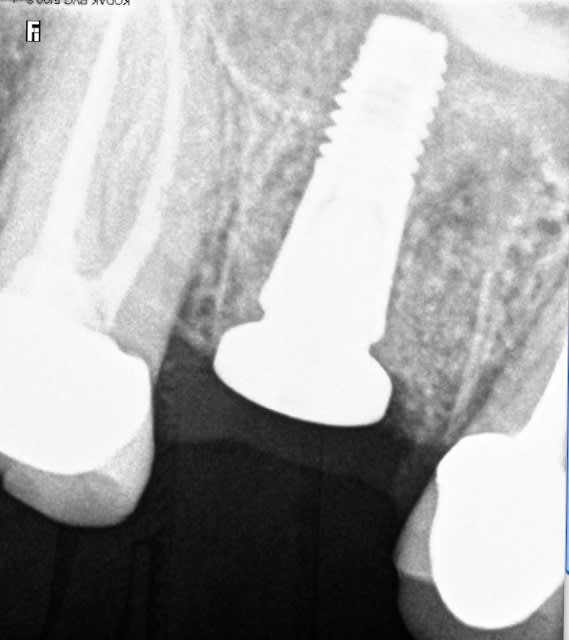

16 extraite, soulevé de la membrane sinusienne au piezo et pose d'un implant dans la foulée, comblement de l'alvéole au Bio-Oss.

C'est un 4,5mm là, j'aurais pu effectivement poser un 5mm,

1) mais ça n'aurait pas changé grand chose là

2) ça m'aurait obligé à passer un fôret dans ce cas là

3) j'avais toujours la possibilité de mettre un 5 au cas ou je n'arrive pas à stabiliser l'implant,

parce que là j'ai 3 ou 4 mm d'os maxi.

bien dans l'axe!

c'est de loin le plus dure! tu fais un pré-forage à la turbine pour respecter ton axe et ne pas te laisser entrainer par les alvéoles des racines ?

oui c'est le plus dur, non tout avec le piezo tu glisses pas, c'est un peu long mais c'est facile.